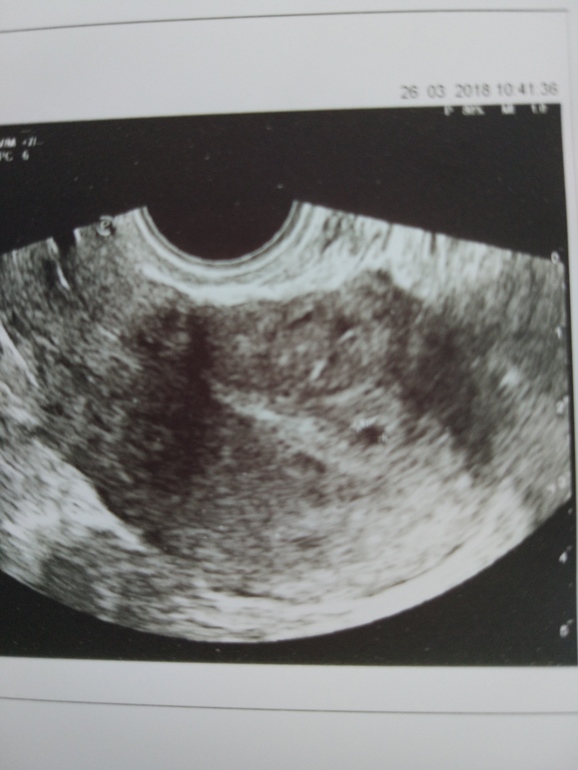

БеременностьУ меня 4 детей и всё путём кесарево сечение,на 4 кесарево порекомендовали врачи сделать перевязку труб .Так и сделала,вот прошло 4 года и вдруг задержка ,боли в низу живота ,потягивает ,левый бог болел, хотелось спать ,тошнило один день.Решила сделать тест отрицательно,но думаю вроде же сделала перевязку.Сегодня была на УЗИ и у гинеколога,врач написала СВД 3,6 мм,на УЗИ показала точку говорит беременность под вопросом.Завтра сдам кровать на ХГЧ,и в четверг к врачу на приём.Сдала ещё мазки .Вот теперь сижу и думаю ждать чуда или нет.Модет у кого-то наступала беременности после перевязки.Фото УЗИ приложила

Здравствуйте ХГЧ пришёл 80 ,врач сказала что слишком мало для срока который она предполагает ,сдаю сегодня ещё раз и в понедельник повторное УЗИ .Пока ни чего не понятно .